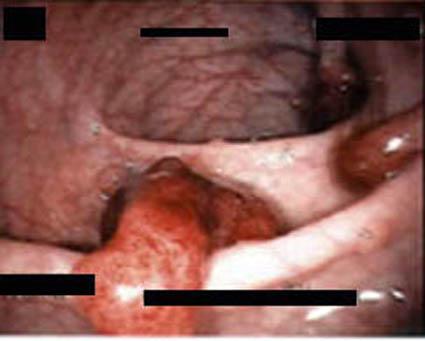

중국요녕성 종괴병원에서의 가족성 대장 용종증의 1례(시행적 등록)

[Image-ID:2201]

질환(병리주체)의 분류

대장 선종증(가족성 대장 용종증 및 Gardner증후군)/

부위(장기별)

대장/기타

검사방법

내시경

종양의 최대경(밀리미터)

15~19